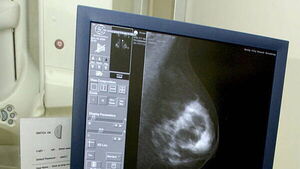

Mother of three Aine McSweeney from Clonmel, Co Tipperary, also claims that she had two mammograms in 2020 and 2022, which she says were allegedly incorrectly interpreted as benign.

In the proceedings, it is claimed that Ms McSweeney had two mammograms at the Breast Clinic in University Hospital Waterford in 2020 and 2022, which were reported back as benign.

It is claimed that these should have been reported as being indeterminate. It is contended that the two mammograms allegedly showed clustered calcifications. If the two mammograms had been followed through, the McSweeny side contends there would have been an investigation and treatment.

In the proceedings, it was claimed that an alleged incorrect interpretation was given in a radiology report of a mammogram of October 23, 2020 and that the findings were reported as benign when it is claimed it showed clustered microcalcifications in the left breast and allegedly should have been reported as being indeterminate.

It was further claimed there was an alleged incorrect interpretation of a January 7, 2022 mammogram, which was reported as benign and which, it is claimed, should also allegedly have been reported as being indeterminate.